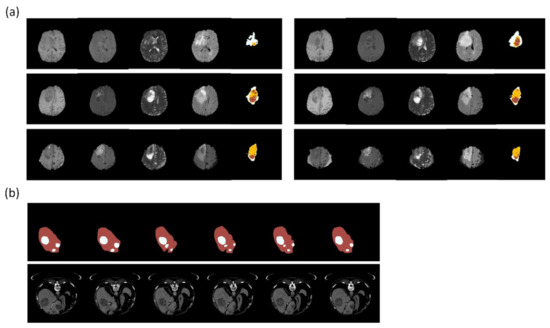

4.2. Brain Lesions

| Zhang et al. [61] (2020) | U-Net | Magnetic resonance images | DSC: 0.62 IoU 6: 0.45 | FPN for extraction first |